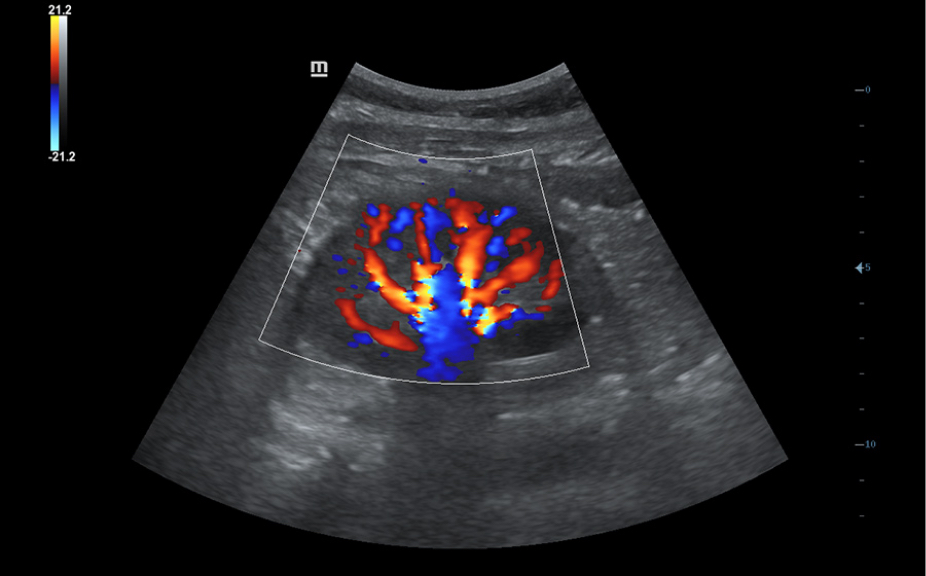

Sistema de diagnĂłstico ecogrĂĄfico

DC- 30

AtenciĂłn primaria con una excelente visiĂłn

FullHD

ImĂĄgenes clĂnicas